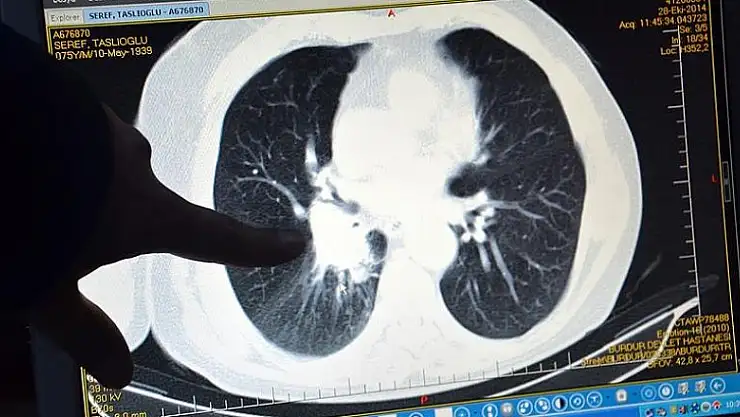

- 'Türkiye'de erkeklerde en sık akciğer kanseri görülüyor'

'Türkiye'de erkeklerde en sık akciğer kanseri görülüyor'

SÜ Tıp Fakültesi Dekanı Prof. Dr. Göktaş, Türkiye'de en sık solunum yolları ve akciğer kanser hastalığının olduğunu, erkeklerde ise en sık akciğer kanseri görüldüğünü söyledi.

Selçuk Üniversitesi (SÜ) Tıp Fakültesi Dekanı Prof. Dr. Serdar Göktaş, Türkiye'de en sık solunum yolları ve akciğer, kalın bağırsak, mide, pankreas kanserleri ile löseminin ölüme yol açtığını belirterek, "Erkeklerde en sık akciğer, prostat, kalın bağırsak, mesane, mide, kadınlarda ise meme, tiroit, kalın bağırsak, akciğer ve rahim kanseri görülmektedir." dedi.

"Ülkemizde en sık solunum yolları ve akciğer, kalın bağırsak, mide, lösemi ile pankreas kanserleri ölüme yol açtı. Erkeklerde en sık akciğer, prostat, kalın bağırsak, mesane, mide, kadınlarda ise meme, tiroit, kalın bağırsak, akciğer ve rahim kanseri görülmektedir." bilgisini veren Göktaş, şunları kaydetti: